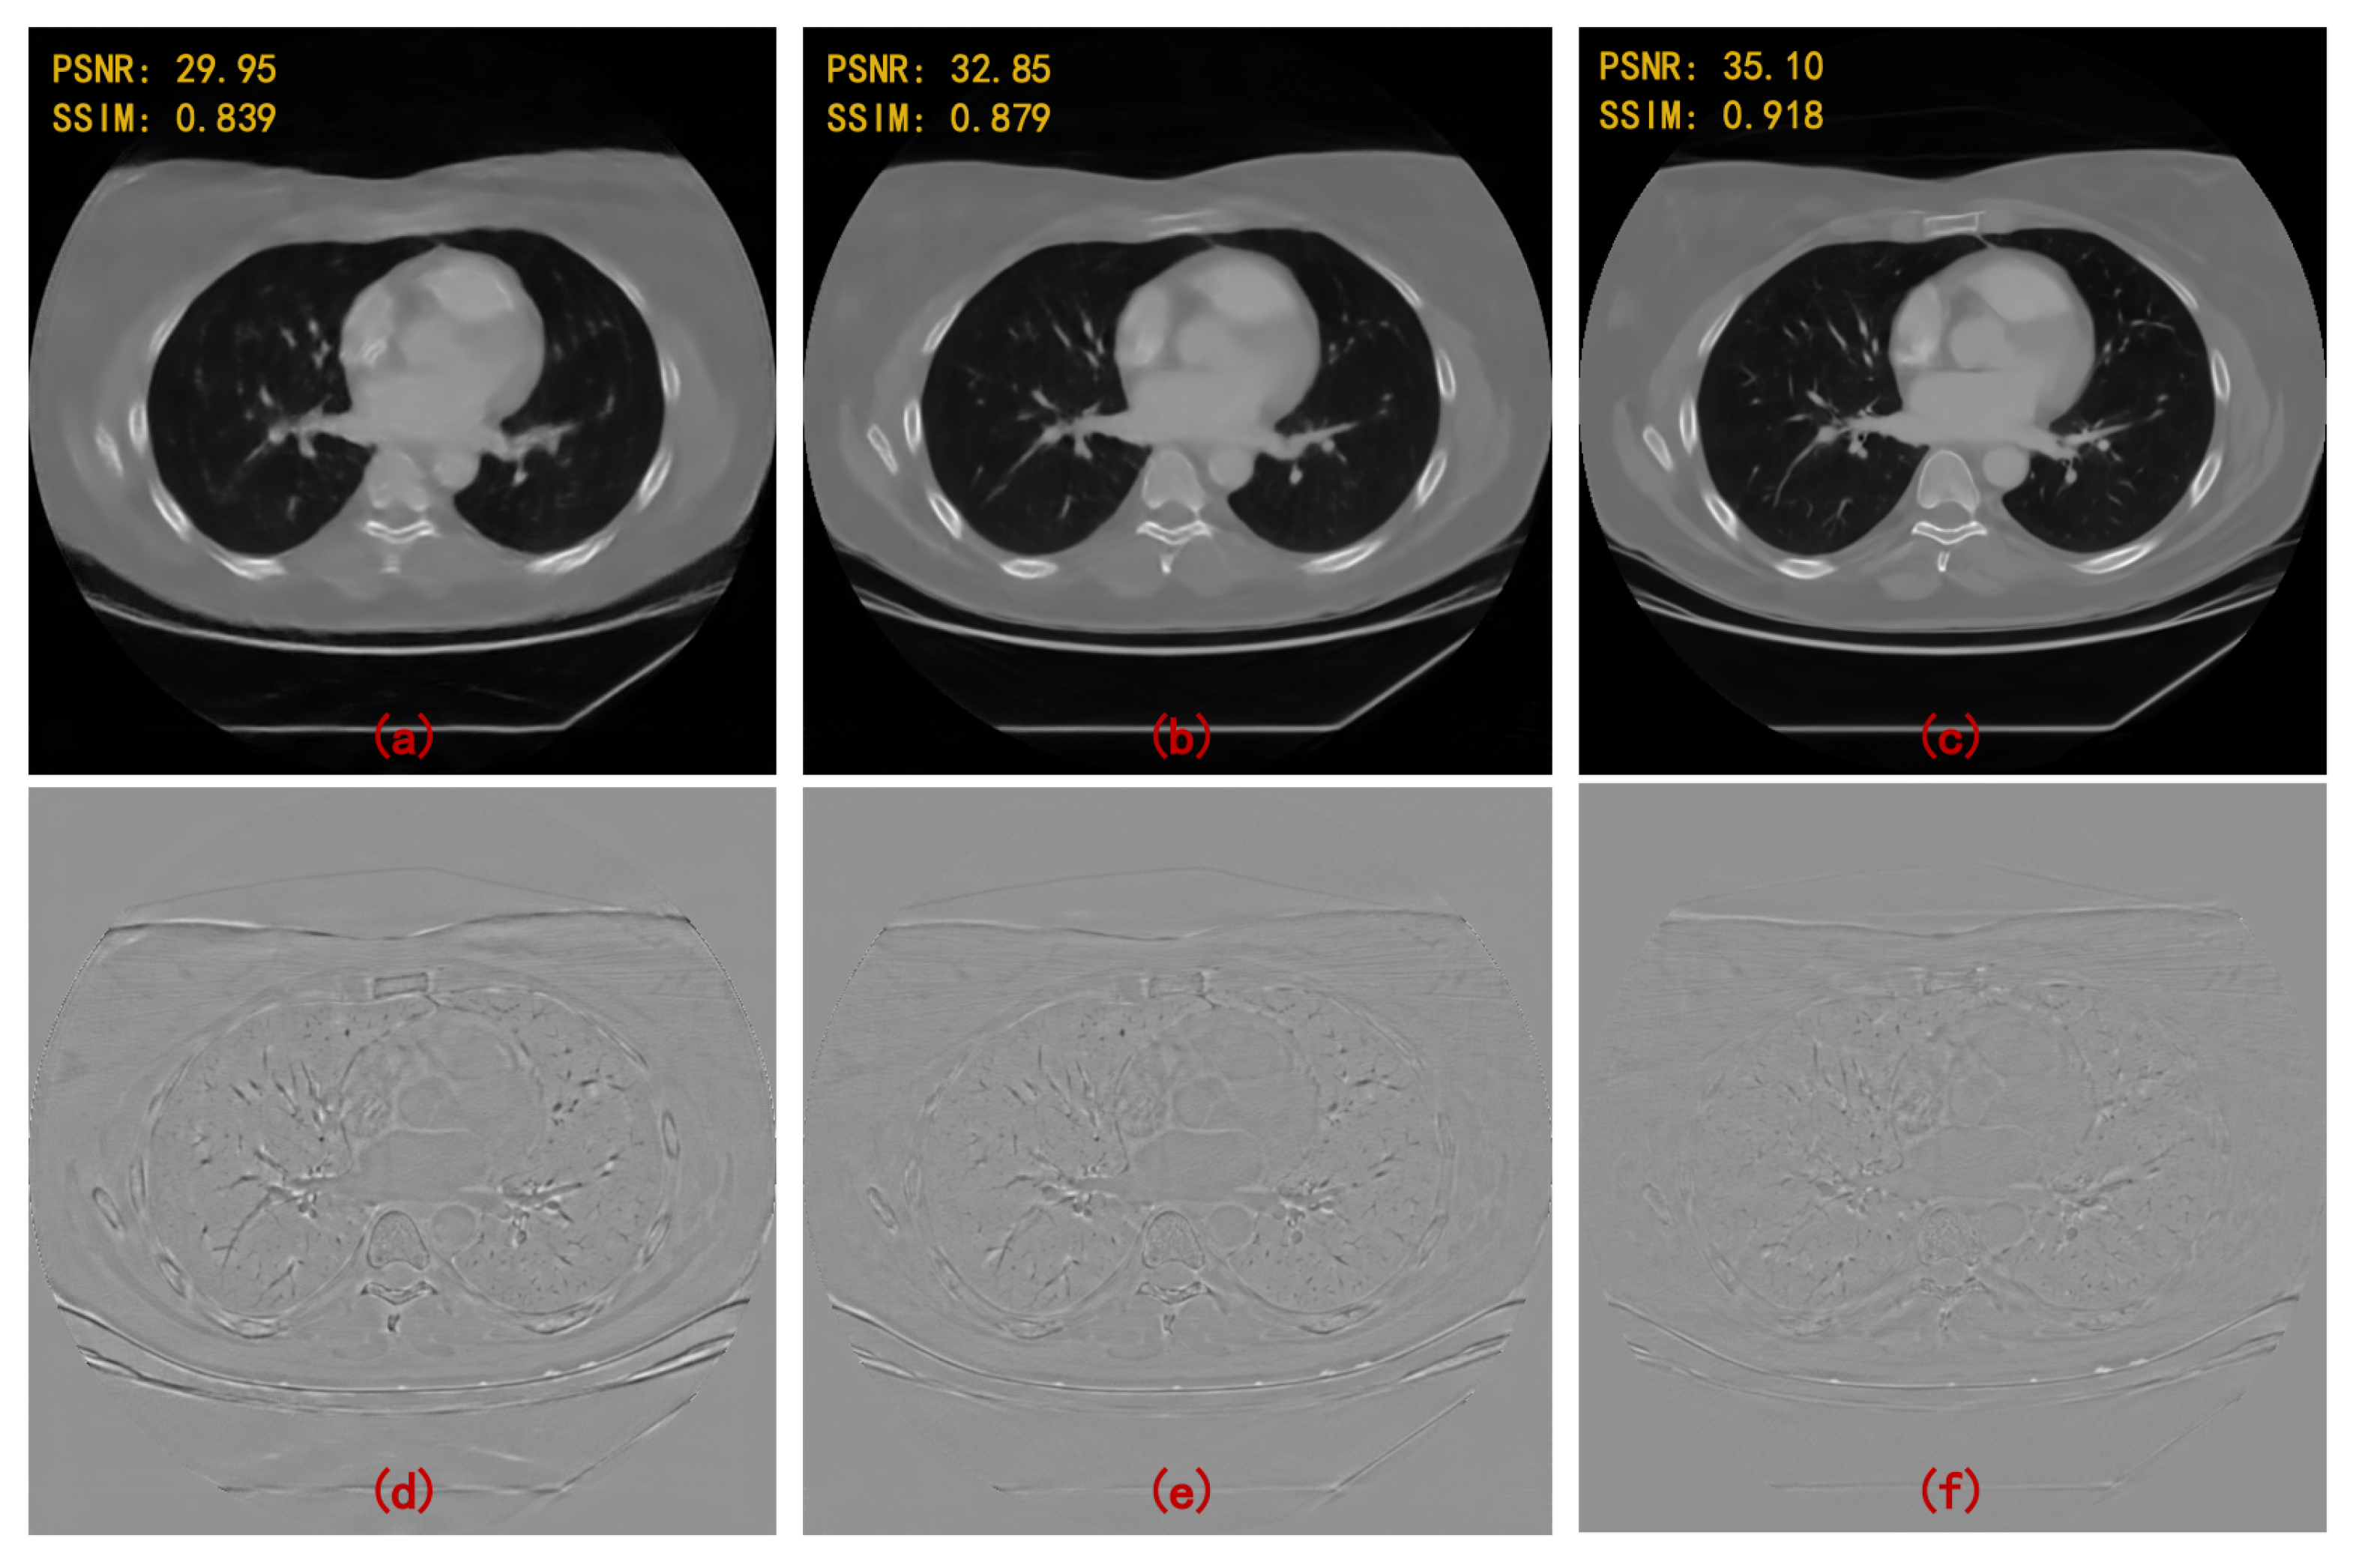

- On the basis of single domain restoration, a hybrid domain reconstruction model for sparse-view CT is proposed, which consists of a projection completion module in radon domain and an image restoration module in image domain. Wavelet domains of projection data and image data are embedded in two modules respectively to better extract spatial features and recover texture details. Moreover, the proposed model is end-to-end learning through the differentiable FBP operator.

- Multi-level wavelet packet decomposition is utilized to replace the pooling operator and enlarge the effective receptive field. Experimental results have shown that a multi-resolution network with a multi-level wavelet transform can effectively suppress globally distributed streaking artifacts.

- A deep residual learning framework is proposed to learn artifacts. Once the artifacts are estimated, an artifact-free image can be obtained by subtracting the estimated results.